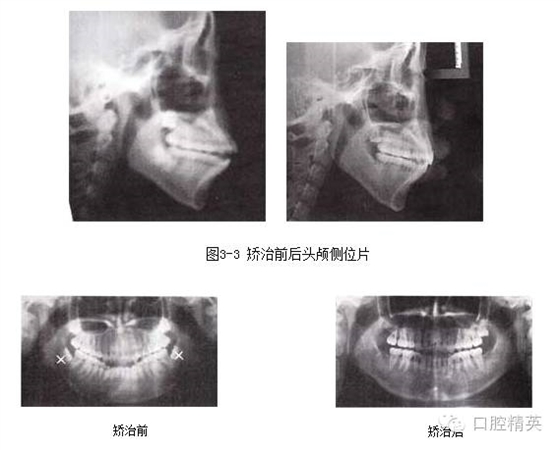

圖3-4 矯治前后全口曲面斷層片

1.前牙開頜,伴有擁擠和輕度前突,上下前牙唇傾,拔除4顆前磨牙,可以解除擁擠,在內(nèi)收前牙的同時,除了可以改善面型突度,通過“鐘擺效應”可以加深覆頜。

2.下頜選擇拔除第二前磨牙,有利于調整磨牙關系由偏遠中至標準中性。

4.阻生第三磨牙的拔除對于開頜的矯治效果及療效的穩(wěn)定十分關鍵。

5.開頜患者通常會伴有后牙的近中傾斜,MEAW技術的應用可以壓低并直立磨牙,有利于開頜的矯治。在MEAW使用過程中,需要將第二磨牙納入矯治序列。同時強調在前牙區(qū)使用垂直牽引。

6.矯治結束后,覆頜覆蓋正常,磨牙關系達到中性,后牙直立。